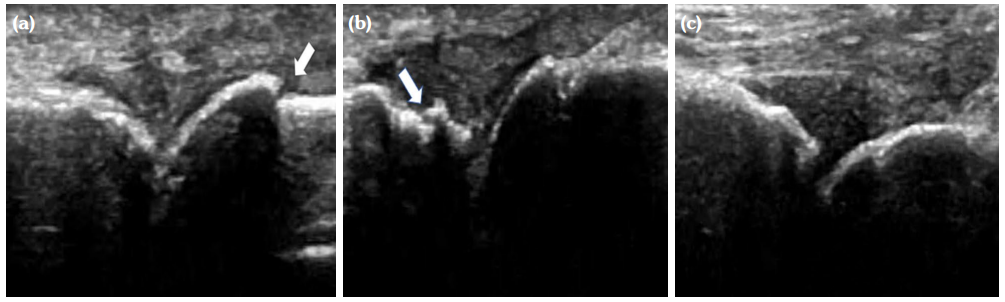

The degree of BE and synovial hyperplasia in SNRA or SPRA is more serious, and the blood flow signal is more abundant. However, the degree of synovial hyperplasia in osteoarthritis was mild, and no obvious blood flow signal was detected (Figures 1, 2, 3 and 4). Magnetic resonance imaging (MRI) studies of SPRA also showed serious BE (Figure 5).

Among SNRA, SPRA and non-RA, there was no significant difference in the grades of SH, PD, BE, nor the number of cases of tendinitis and tenosynovitis between the SNRA group and the SPRA group (p>0.05) (Table 3). There were, however, statistically significant differences in the number of cases of SH1, SH3, PD and BE grades between the SNRA and non-RA groups (p<0.001). There was no significant difference in the number of cases of SH2, PD2, tendinitis or tenosynovitis between the SNRA and non-RA groups (p>0.05) (Table 4).